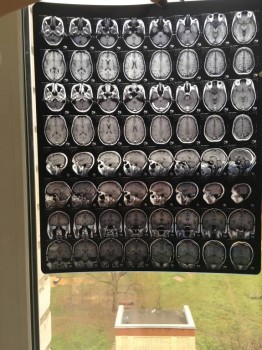

Общалась с Вами по телефону неделю назад, после того как мне на МРТ продиагностиргвали кисту шишковидной железы головного мозга.

Отправляю Вам снимки МРТ, Очень надеюсь на вообще мнения о причине возникновения кисты.

Снимок позвоночника

Здравствуйте, Евгения. Пленки мрт желательно смотреть (зная и видя пациента) на специальном экране, в полном размере. Отсюда можно увидеть, что они есть. Не более. Вполне логично, если врачи сделают заключение по месту проведения исследования. Если останутся сомнения, проконсультируйтесь в другой клинике, только отвезите сами снимки.